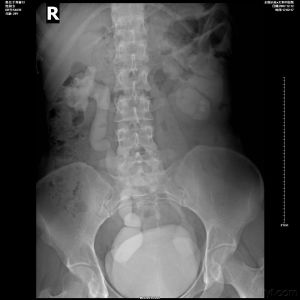

伴有尿路感染及結石時尿液檢查可有紅細胞、白細胞及致病菌。膀胱鏡檢查三角區和輸尿管開口位置一般正常,成人尤為如此。輸尿管導管插入可毫無困難。早期病例造影X射線片僅見輸尿管下段呈紡錘狀或球狀擴張;注射造影劑後立即拔出輸尿管導管拍攝排空片,可見造影劑滯留及延遲排空現象。

X射線攝片中可見到輸尿管內造影劑有逆蠕動反流到腎臟的現象。

根據X射線尿路造影,還可觀察腎盞與腎實質的形態變化,從而可估計其受損程度。

腎盞:腎盞可從正常、腎盞杯口平坦、杯口不規則、隆起外凸,直到腎盞球形擴展等發生不同程度的變化。

腎實質:腎實質可從厚度正常(一般在2cm以上)、厚度在1~2cm之間,直到厚度變薄(兒童在1cm以下嬰,幼兒在0.5cm以下)等出現不同程度的損害。

B超:可見患側輸尿管擴張,有腎積水或無明顯腎積水。

CT及MRI:CT可見到全程輸尿管擴張,可有不同程度的腎積水,輸尿管膀胱交界處可見到狹窄。MRI可見到擴張輸尿管全貌,下端狹窄,可伴有腎積水。